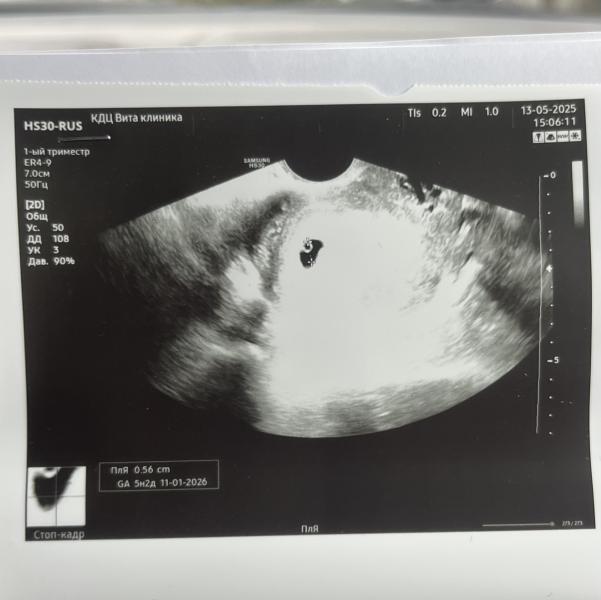

Спонтанно решила сходить на второе узи😅

Увидели эмбрион и сердечко🥹🫶🏻

По месячным 6.6

По узи ставят 6 ровно (?)

Подскажите, пожалуйста, все в норме?

Не могу найти количество ударов сердца в минуту, она не написала, да?(

Первая встреча с креветкой✨